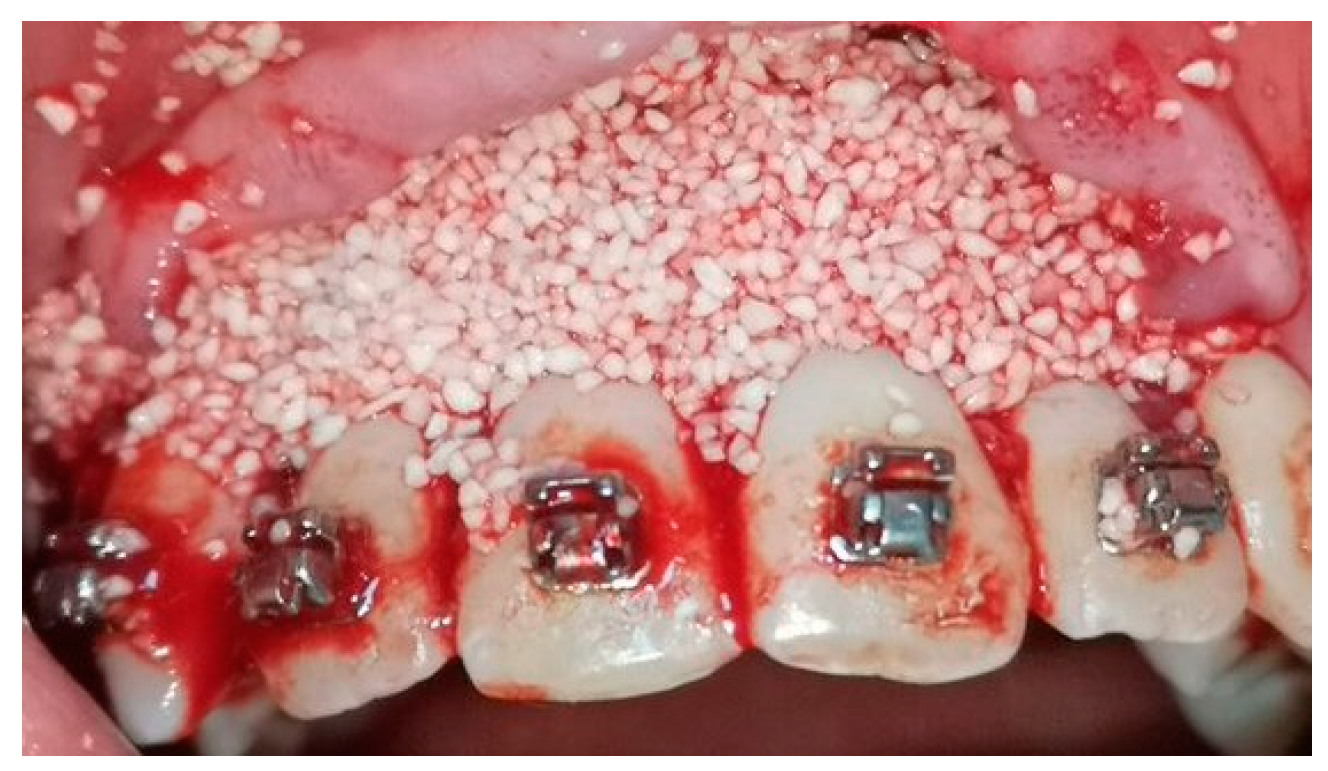

2.5. Surgical Phase